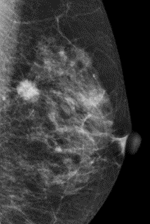

マンモグラフィ検査は、乳房を板で挟んでやや圧迫した状態でX線(乳房専用撮影)を行い、乳房内部の構造や石灰化、腫瘤(しこり)の有無を画像で確認する検査です。

乳房内に現れる異常陰影や微細な石灰化を探すのに非常に有効で、乳がんの早期発見に欠かせない検査の一つです。

さらに圧迫時間も以前より短くなり、被ばくも基準の半分以下で撮影可能です。乳がんの代表的な病変である腫瘤・石灰化をマンモグラフィにて観察することが出来ます。

上の図の白く濃く塊のように見えるのが乳がんの所見です

(乳がんの所見の一例です。)